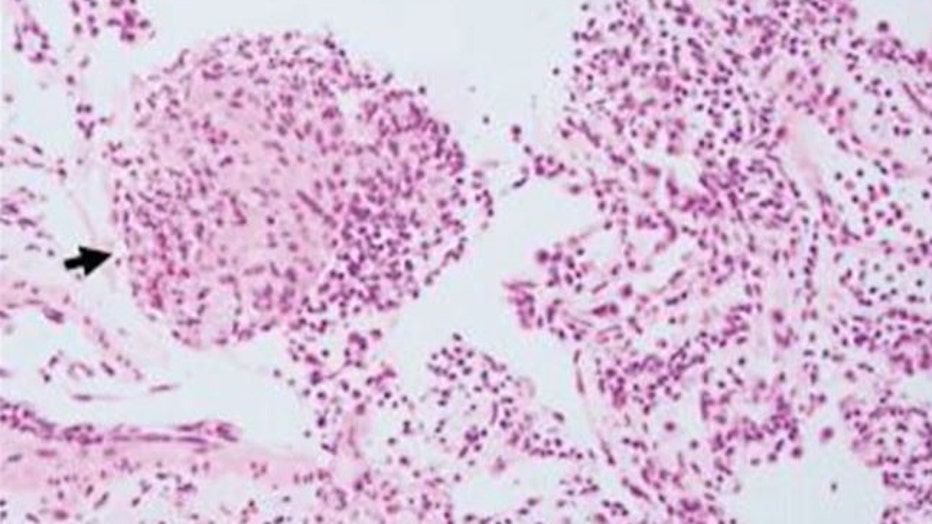

Doctors removed a worm "still alive and wiggling" from a woman's brain. (Credit: Australian National University via Storyful)